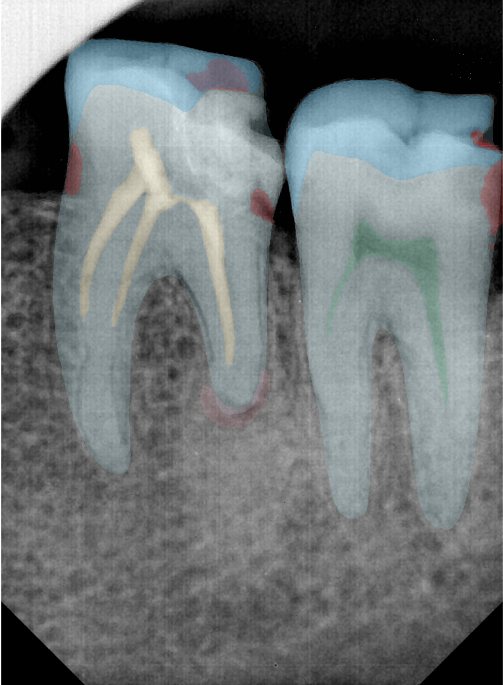

CR/DR 牙齿分割阶段记录

当前进展

- 完成了 CR/DR 牙齿相关分割训练

- 当前结果已经达到阶段预期,但仍有细节问题需要继续处理

相关测试

遇到的问题

- 训练过程中出现过 mask 下移问题

- 部分结果会出现 box 填充异常

- mask 边缘仍然有比较明显的锯齿感

参考

第三版算法分辨率效果比较

Updated: 2026-04-13(更新日期)

| 编号 | 原图 | 第一版 | 第二版 | 第三版 1216x1600 | 第三版 768x1024 | 第三版 1120x1120 |